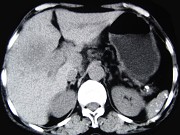

- 单项选择题女,65岁, 右季肋区疼痛二个月,CT扫描所见如图, 最可能的诊断为( )